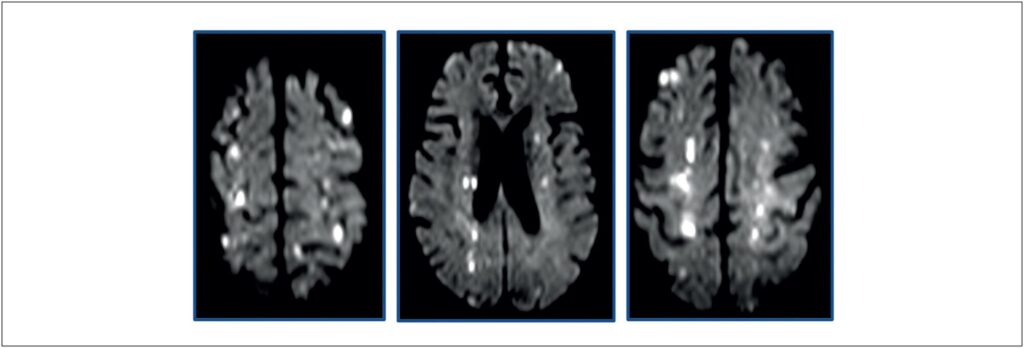

Aortic Valvulitis in Hypereosinophilic Syndrome: A Case Report

Keywords: Aortic Valve Disease; Hypereosinophilic Syndrome; Stroke